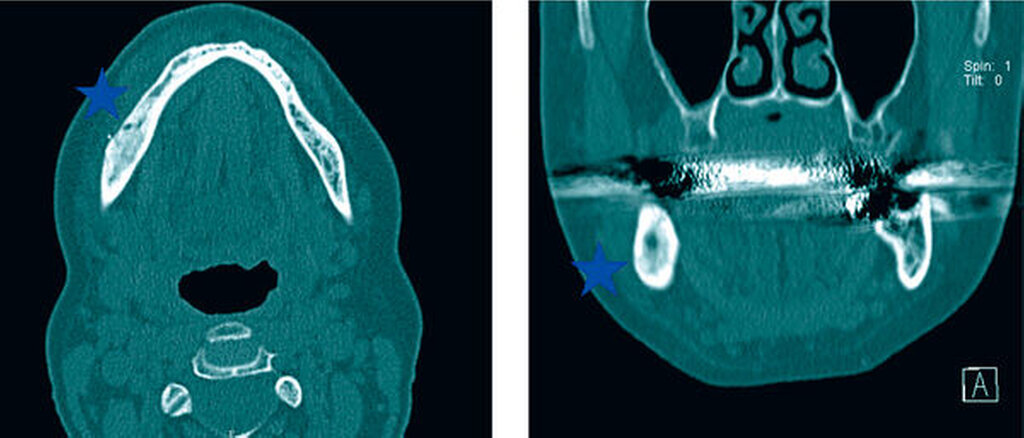

In radiologischen Untersuchungen zeigt sich bei konventionellen Röntgenaufnahmen und in der CT-Bildgebung im betroffenen Kieferareal eine vermehrte Sklerosierung des Knochens ohne Sequesterbildung (Abbildungen 1 bis 3). In der Szintigrafie des Unterkiefers zeigt sich ein chronisch entzündlicher Prozess ohne Anzeichen für eine floride bakterielle Entzündung [van Merkesteyn et al., 1988] (Abbildung 3).